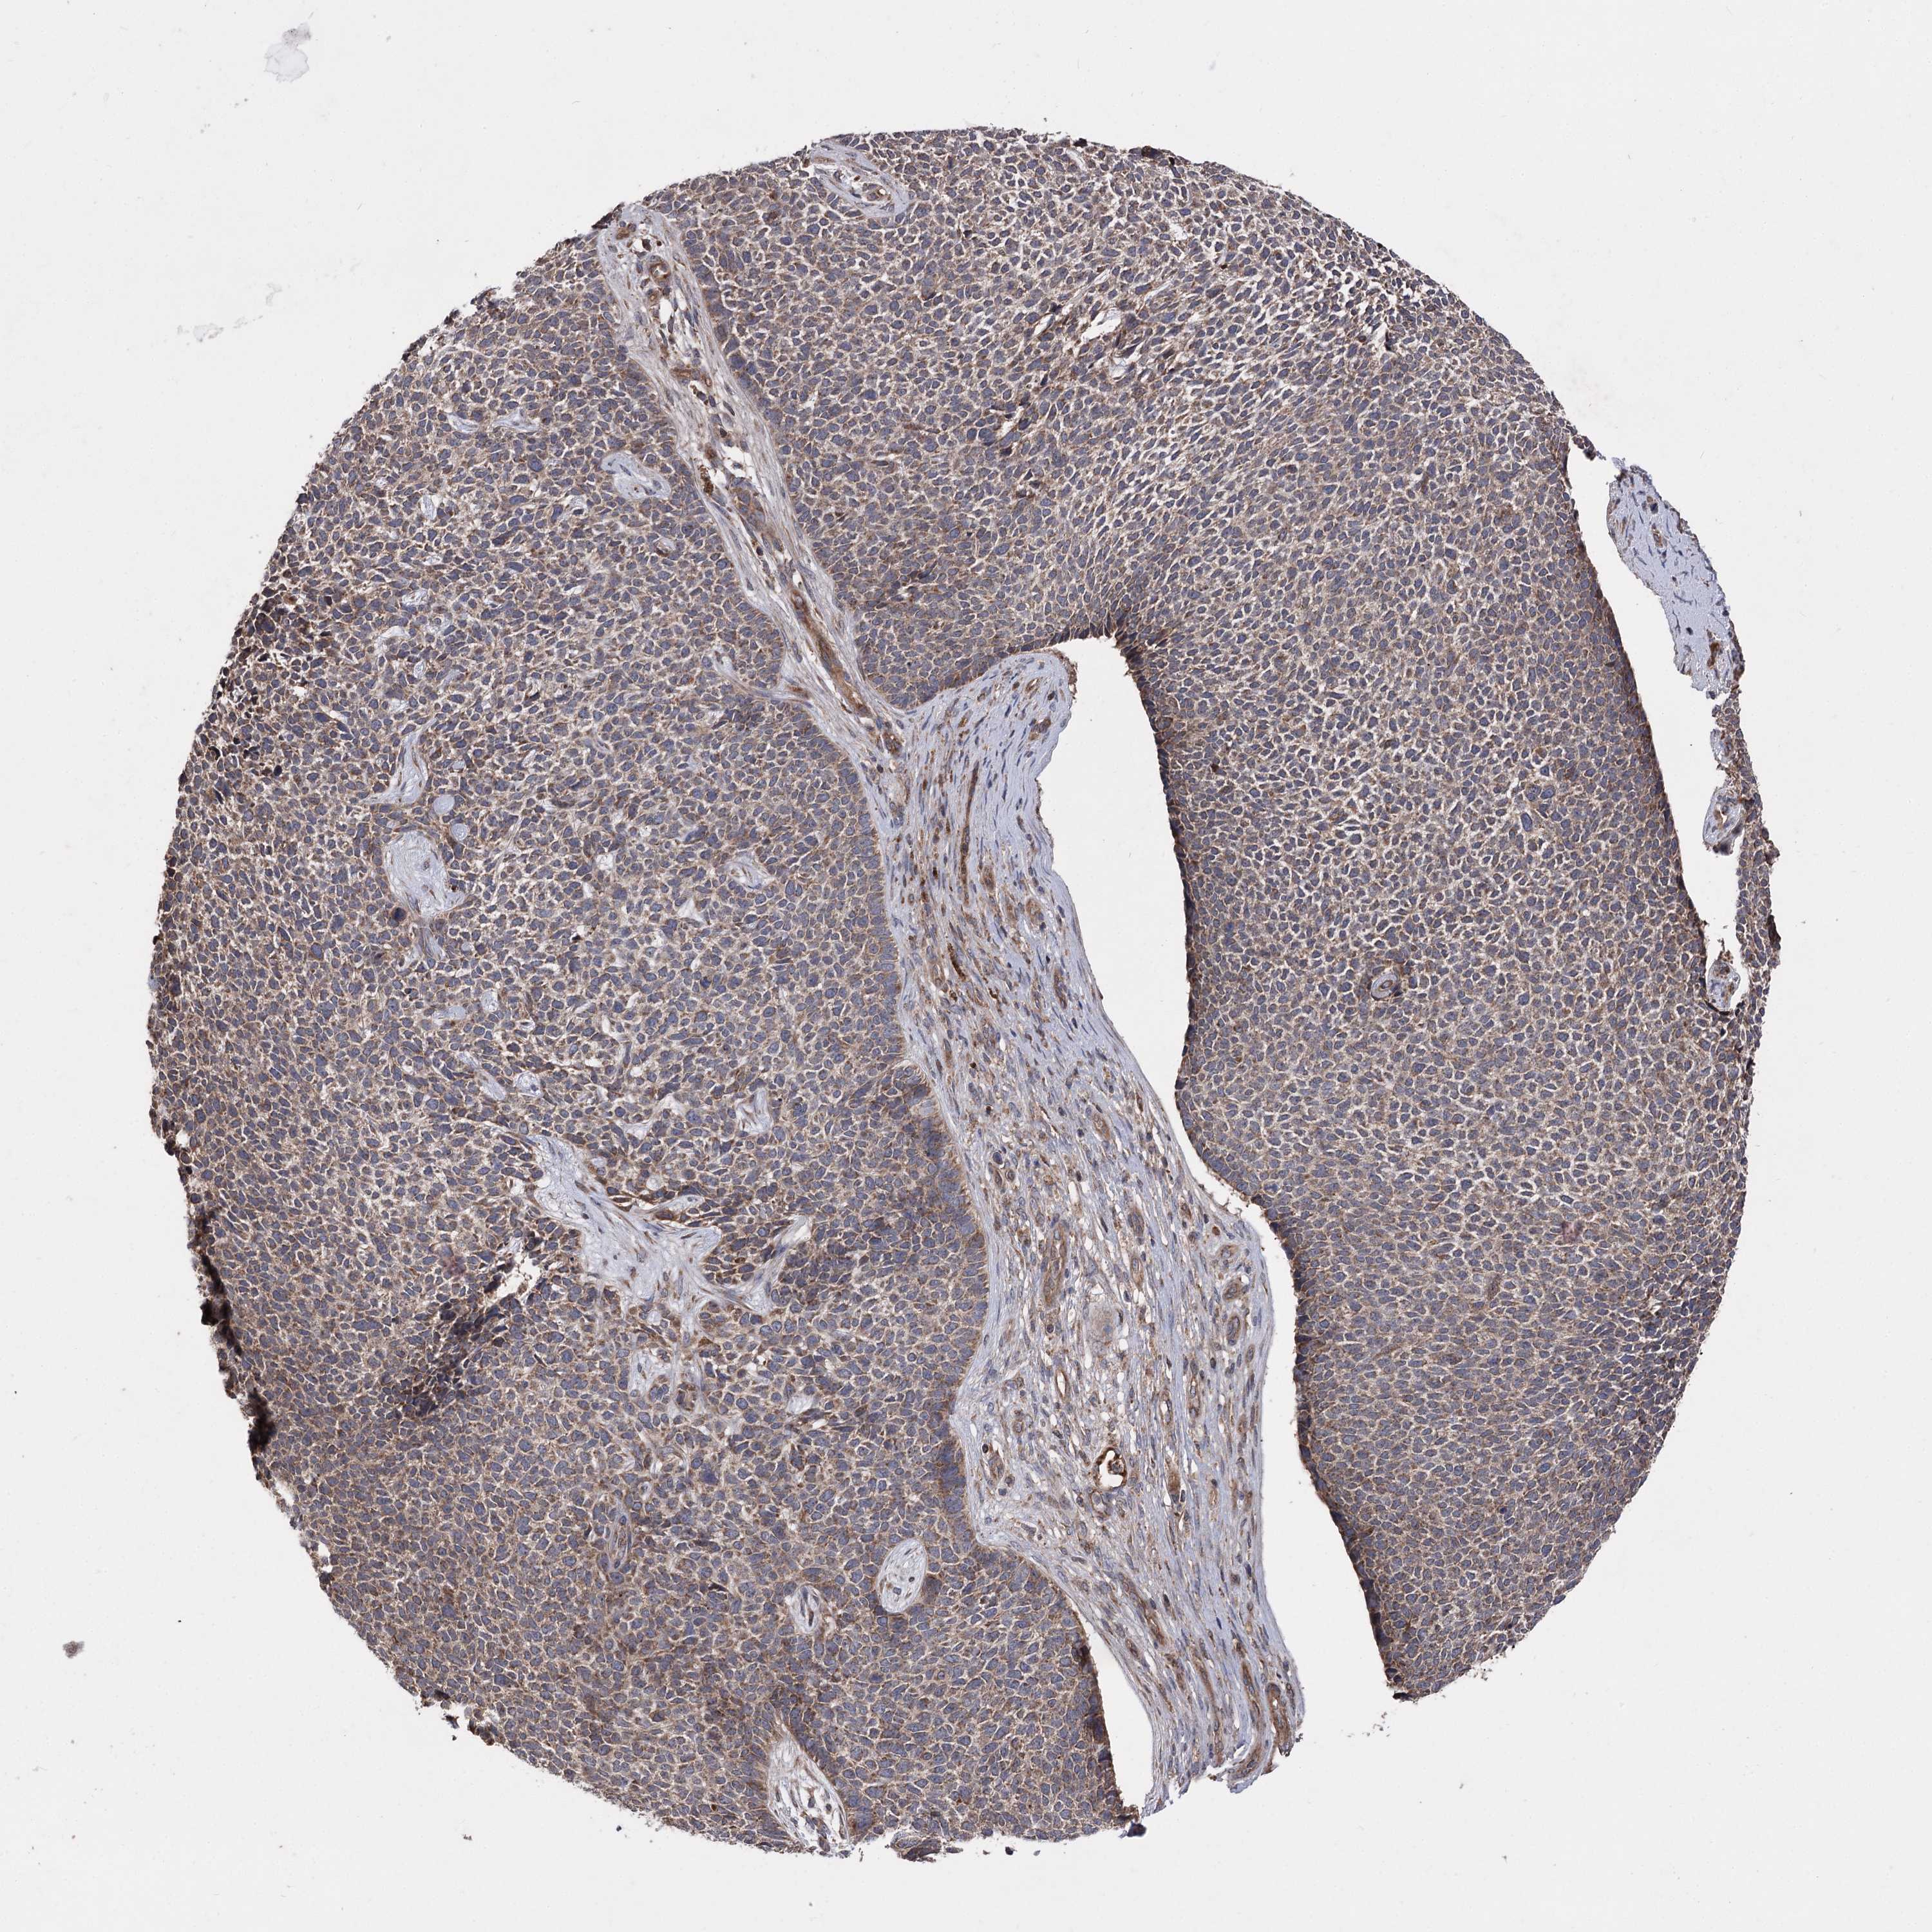

SKIN CANCER - Protein expressioni

A mouse-over function shows sample information and annotation data. Click on an image to view it in a full screen mode. Samples can be filtered based on level of antibody staining by selecting one or several of the following categories: high, medium, low and not detected. The assay and annotation is described here.

Antibody staining in the annotated cell types in the current human tissue is reported as not detected, low, medium, or high, based on conventional immunohistochemistry profiling in selected tissues. This score is based on the combination of the staining intensity and fraction of stained cells.

Each image is clickable and will lead to virtual microscopy that enables deeper exploration of all samples and also displays staining intensity scores, fraction scores and subcellular localization as well as patient and tissue information for each sample.

Basal cell carcinoma